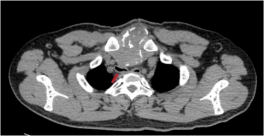

2. 纵隔肿瘤切除手术

纵隔肿瘤手术前 | 纵隔肿瘤手术后 |